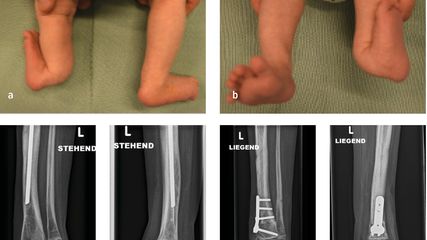

Zusätzlich: Die Finger 1–3 liegen hinter dem Ohr, Finger 4–5 vor dem Ohr (Abb. 2). Beim Einatmen Fussspitzen nach oben ziehen, 5 Sekunden Luft anhalten, dabei den Unterkiefer nach unten ziehen. Beim Ausatmen lockerlassen und die Fussspitzen nach unten bewegen. 3x wiederholen.